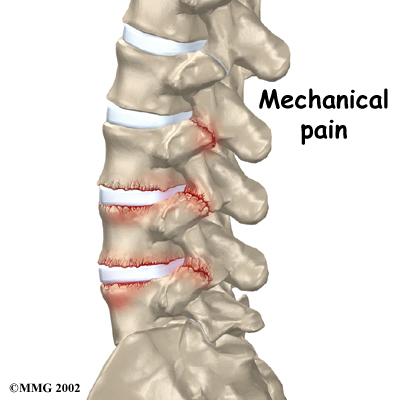

The main goal of the spinal fusion (also known as an arthrodesis) is to stop movement of one or more vertebrae. Keeping the fused section from moving helps stop mechanical pain. Mechanical pain occurs when damaged discs and joints that connect the vertebrae become inflamed from excessive motion between the vertebrae. This type of pain is commonly felt in the low back and may radiate into the buttocks and upper thighs.